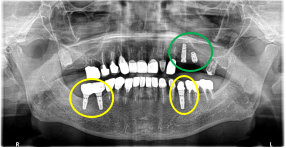

Before

※赤丸は、歯根が破折していたため抜歯しました

※黄色丸は、2006年10月に埋入したインプラント

After

※緑丸は、今回埋入したインプラント